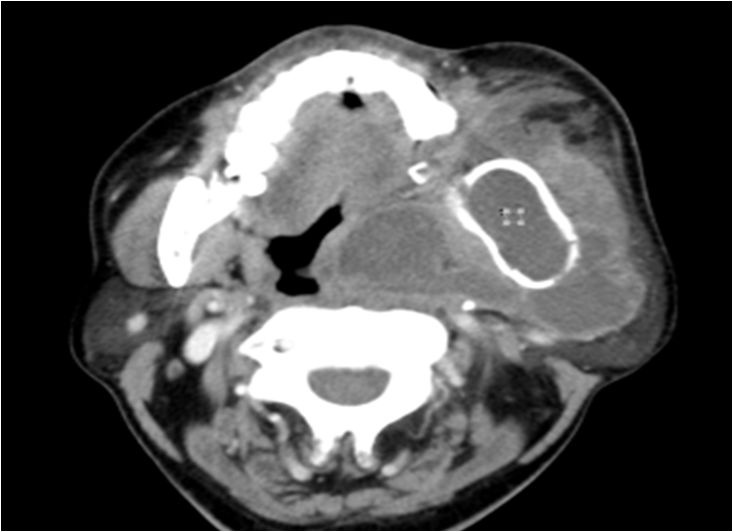

15 多间隙受累

(1)左下后牙疼痛11天余,颈部肿胀10天。

(2)右侧颌面部弥漫性肿胀1月余。